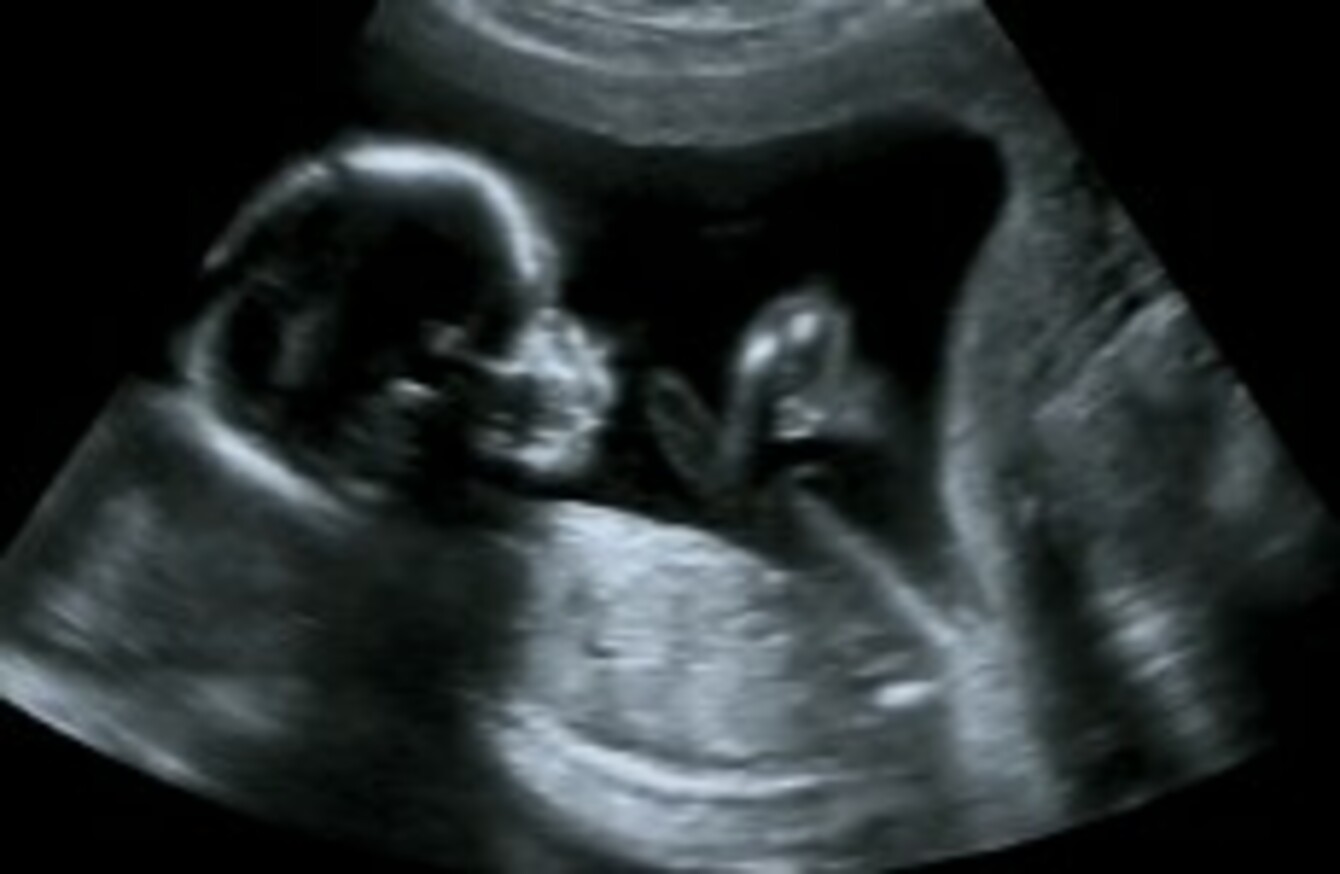

Though it is rare it is possible to have a hidden twin that is not visible during early ultrasound screenings. The abdominal scan may miss it a transvaginal ultrasound will pick up the baby by the six weeks but it also miss it in this period. I dont know if I should get an abor bleeding between periods with slight cramps and bloating ag Painful Ultrasound Hard lump in lower abdomenbelly Feel Pregnant but did not miss period.

I had no signs of mc before that. Apparently twins can hide behind I e another completely for up to 29 weeks. Are You Carrying Twins.

Hidden twins are more common with early ultrasound because the baby is. A pregnancy that doesnt show on an ultrasound scan is called a pregnancy of unknown location. In the case of ectopic pregnancy a small opening grows inside the uterus similar to what happens in very early pregnancy but theres no baby there. Abdur-Rahman says while pretty uncommon you really can have a so-called hidden twin. Noticed that Baby A had a heartrate significantly lower than baby Bs so they scheduled another ultrasound 2 weeks later at 8 weeks and at this. Also i was measuring off by a week n ahalf. Though it is rare it is possible to have a hidden twin that is not visible during early ultrasound screenings. Can a baby hide from ultrasound. Your first pregnancy ultrasound is usually an exciting event.

Determining a fetus sex on ultrasound is certainly more difficult in women who are. Sixth pregnancy Hormone levels are sky high ultrasound cant find baby. A pregnancy that doesnt show on an ultrasound scan is called a pregnancy of unknown location. While he did mention it may be just be too soon to detect he also said that it may be ectopic. This is particularly true in the early months of pregnancy. But some how during the ultrasound she got her cord down between her legs. Though it is rare it is possible to have a hidden twin that is not visible during early ultrasound screenings.